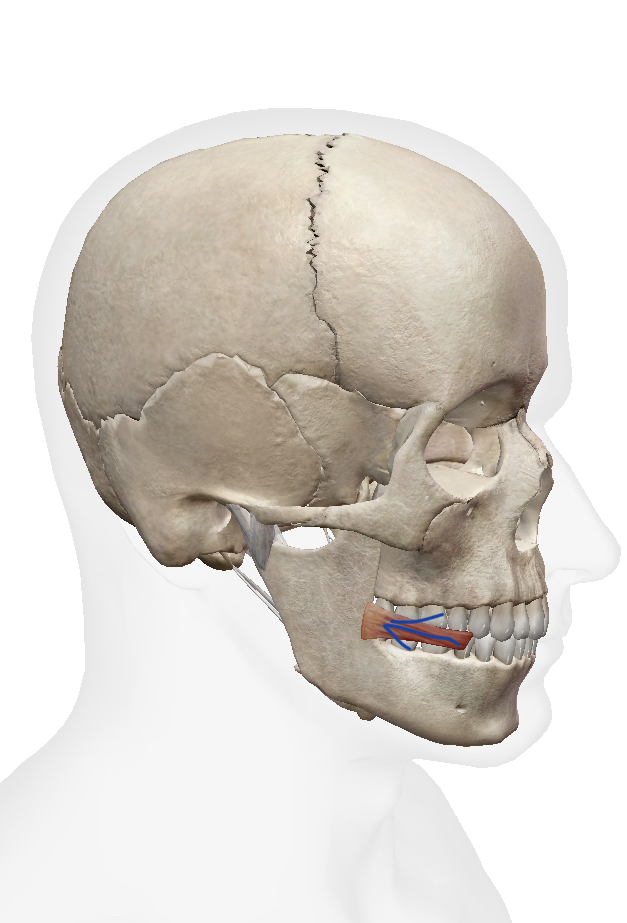

顔には眉や頬、口など様々な部位を動かして表情を作り出す表情筋があります。同じ筋肉を使っていると皮膚の形状記憶によりシワが残りやすく、反対に使っていない筋肉があると表情筋が低下し、たるみによるシワの原因にもなると考えられています。

表情筋はたくさんの筋肉がありますが、今回はその中で意識しやすい主な表情筋を5つ紹介していきます。

・前頭筋:眉上から額全体にかけて縦に伸びている筋肉。眉を上下に動かす役割がある。

・眼輪筋:目の周囲に位置し、目の開閉運動を担う。

・頬筋:上顎の関節から口角にかけて発達している筋肉で、口角を上げる働きをしている。

・口輪筋:口の周囲にある筋肉で、口元の表情を作る動きをしている。

・笑筋:口元から左右の頬にかけて発達している筋肉で、微笑んだ表情やえくぼを作る。

マッサージをするときは、それぞれの筋肉の方向に沿ってほぐすと良いです![]()